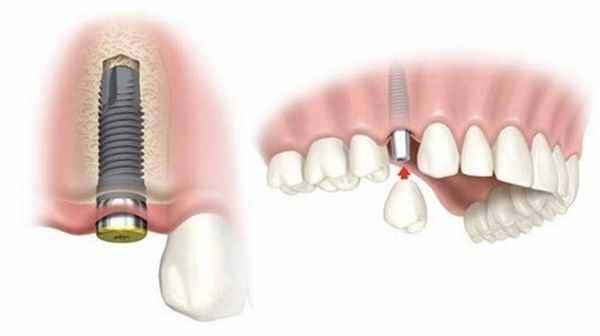

Нетравматичное удаление зуба и отсутствие болевых ощущений у пациента являются обязательными условиями успешного проведения последующей имплантации и протезирования.

Для многих людей имплантация зуба является самым надежным и оптимальным вариантом восстановления зубного ряда. Существует несколько разновидностей имплантации зубов, наиболее быстрым из которых считается одномоментная имплантация. Особенностью этой манипуляции является то, что удаление зуба и установка импланта происходит сразу друг за другом во время одного визита к стоматологу. Именно при проведении этого вида вмешательства огромное значение имеет безболезненное удаление зуба перед имплантацией, деликатно и не травматично. Несоблюдение техники удаления зуба перед одномоментной имплантацией может стать серьезным препятствием к выполнению этой процедуры.

Также минимальная травматизация при удалении зубов важна перед проведением других вариантов имплантации зуба, а также перед остеопластическими операциями. Современные стоматологические клиники предлагают своим пациентам быстрое и удаление зубов без боли с применением современного оборудования и обезболивающих препаратов. Нетравматичное удаление зуба и отсутствие болевых ощущений у пациента являются обязательными условиями успешного проведения последующей имплантации и протезирования.

Основным показанием к проведению одномоментной имплантации зубов является потеря одного или нескольких зубов при соблюдении важного условия, а именно – сохранения нужного объема и прочности челюстной кости.

Удаление зуба является рутинной процедурой для опытного стоматолога. После проведения комплекса подготовительных мероприятий и обезболивания врач приступает к непосредственному удалению зуба. В большинстве случае процедура удаления зуба состоит из отслойки десны при помощи специального инструмента, накладывания щипцов на зуб с последующим аккуратным его расшатыванием. После того, как зуб становится достаточно подвижным, его извлекают из лунки, которую после этого внимательно осматривают, чтобы не допустить наличие в ней костных фрагментов. Завершающим этапом является обработка лунки зуба, основной целью которой является предотвращение инфекционных осложнений.

Иногда перед имплантацией может понадобиться сложное удаление зуба. К этой процедуре прибегают в тех случаях, когда имеются аномалии строения зубного ряда или сильное искривление корней зуба. При сложном удалении стоматолог использует дополнительный инструментарий и вмешательство требует немного большего количества времени. Если удаление зуба прошло атравматично, то врач приступает к процедуре имплантации.